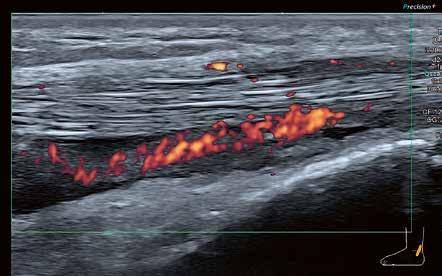

60 Ein Plädoyer für hochwertige Ultraschallausrüstung in der neurologischen Praxis

ULTRASCHALL

Hochauflösender Ultraschall in der Sportpraxis

Wie kamen Sie zur Sonographie?